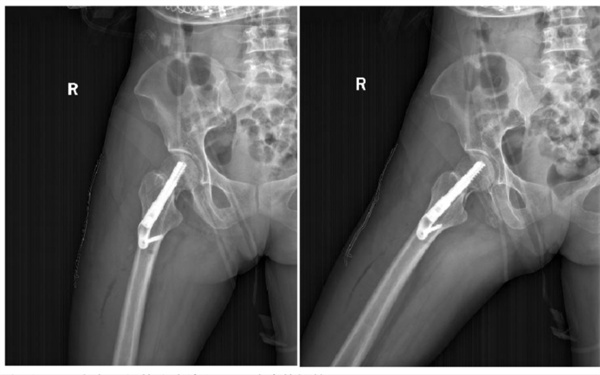

患者王某年仅44岁,骨质状况良好,徐典康副主任医师经过科室团队讨论,评估潜在风险,排除手术禁忌后,决定采用FNS为其实施“保头”手术。手术中,徐典康医师精准操作,顺利完成FNS内固定手术。术后效果理想,骨折对位对线良好,切口小,固定牢固。术后当天患者就能在床上行患肢功能锻炼,1周后可坐床边锻炼,复查X片显示骨折复位、FNS固定良好,后续已康复出院。

术后X片,骨折已完全复位,FNS固定稳妥